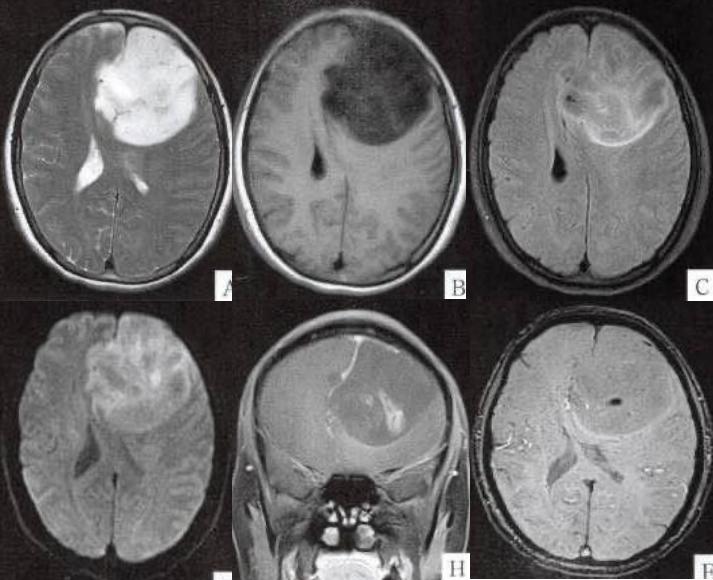

答案:海绵状血管瘤伴出血。海绵状血管瘤属于颅内较常见的一种血管畸形,根据患者颅内血管瘤所处部位的不同可将海绵状血管瘤分为脑内型及脑外型两种。

海绵状血管瘤在颅内的发病部位多见于右脑、左脑及脑干,因血管瘤所处发病的位置不同,不同部位的海绵状血管瘤也将呈现出不同的临床表现,主要表现为颅内出血、头疼、癫痫症状及局限性脑神经功能障碍。影像学表现:CT:表现为富含血管的占位征象。MRI:脑内病灶:病灶与周围脑策划有明确的边界,呈圆形。病灶在T1加权像呈等信号,在T2加权像或注射对比剂后呈高信号,病灶内有混杂低信号,病灶周围有环形低信号带。脑外病灶:以海绵窦区的海绵状血管瘤为例,在MRI表现为T2WI呈极高信号,增强扫描强化非常显著,ADC值明显升高,DWI接近等信号,MRS检查无NAA峰、Cr峰和Cho峰,可以作出定性诊断。总结:脑内圆形或椭圆形病灶,有混杂密度(代表不同程度的出血,MRI的T2像上有含铁血色素的沉积。T2WI成像显示异常信号团块周围有完整的含铁血黄素沉积带包围。这种低信号改变是诊断海绵状血管瘤的重要依据,是含铁血色素的特征性影像改变。(如下图)